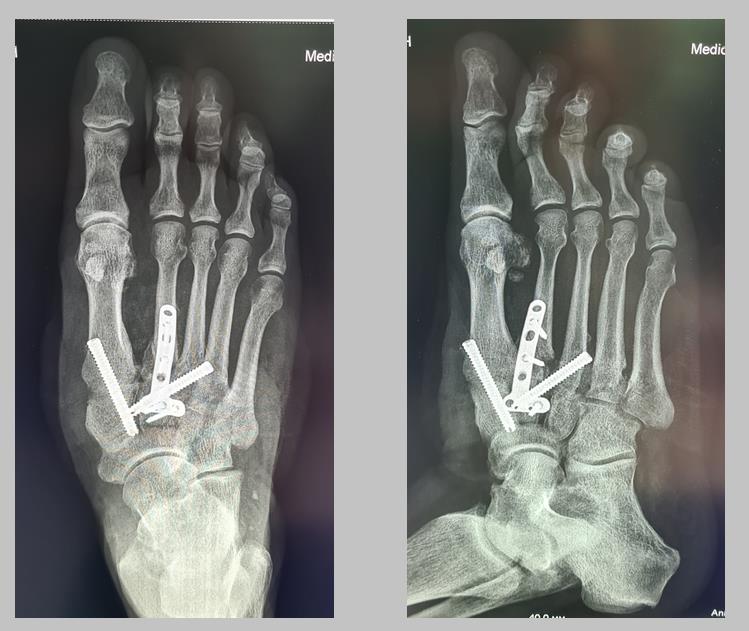

Анатомия суставов Шапарова и Лисфранка: фото и информация